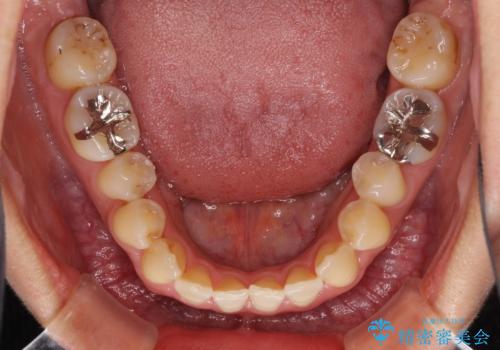

前歯のデコボコ インビザラインによる矯正治療

- 上下前歯の叢生と奥歯の反対咬合を気にして来院された患者様です。

インビザラインを用い、下顎はIPR(歯と歯の間を削る)と歯列全体を後方に移動させ、上顎は側方に拡大させることで歯列を改善していくこととしました。

骨格的に下顎が左側前方にずれているため、上下正中のズレや左右奥歯の咬み合わせを理想的な状態とすることは困難でした。